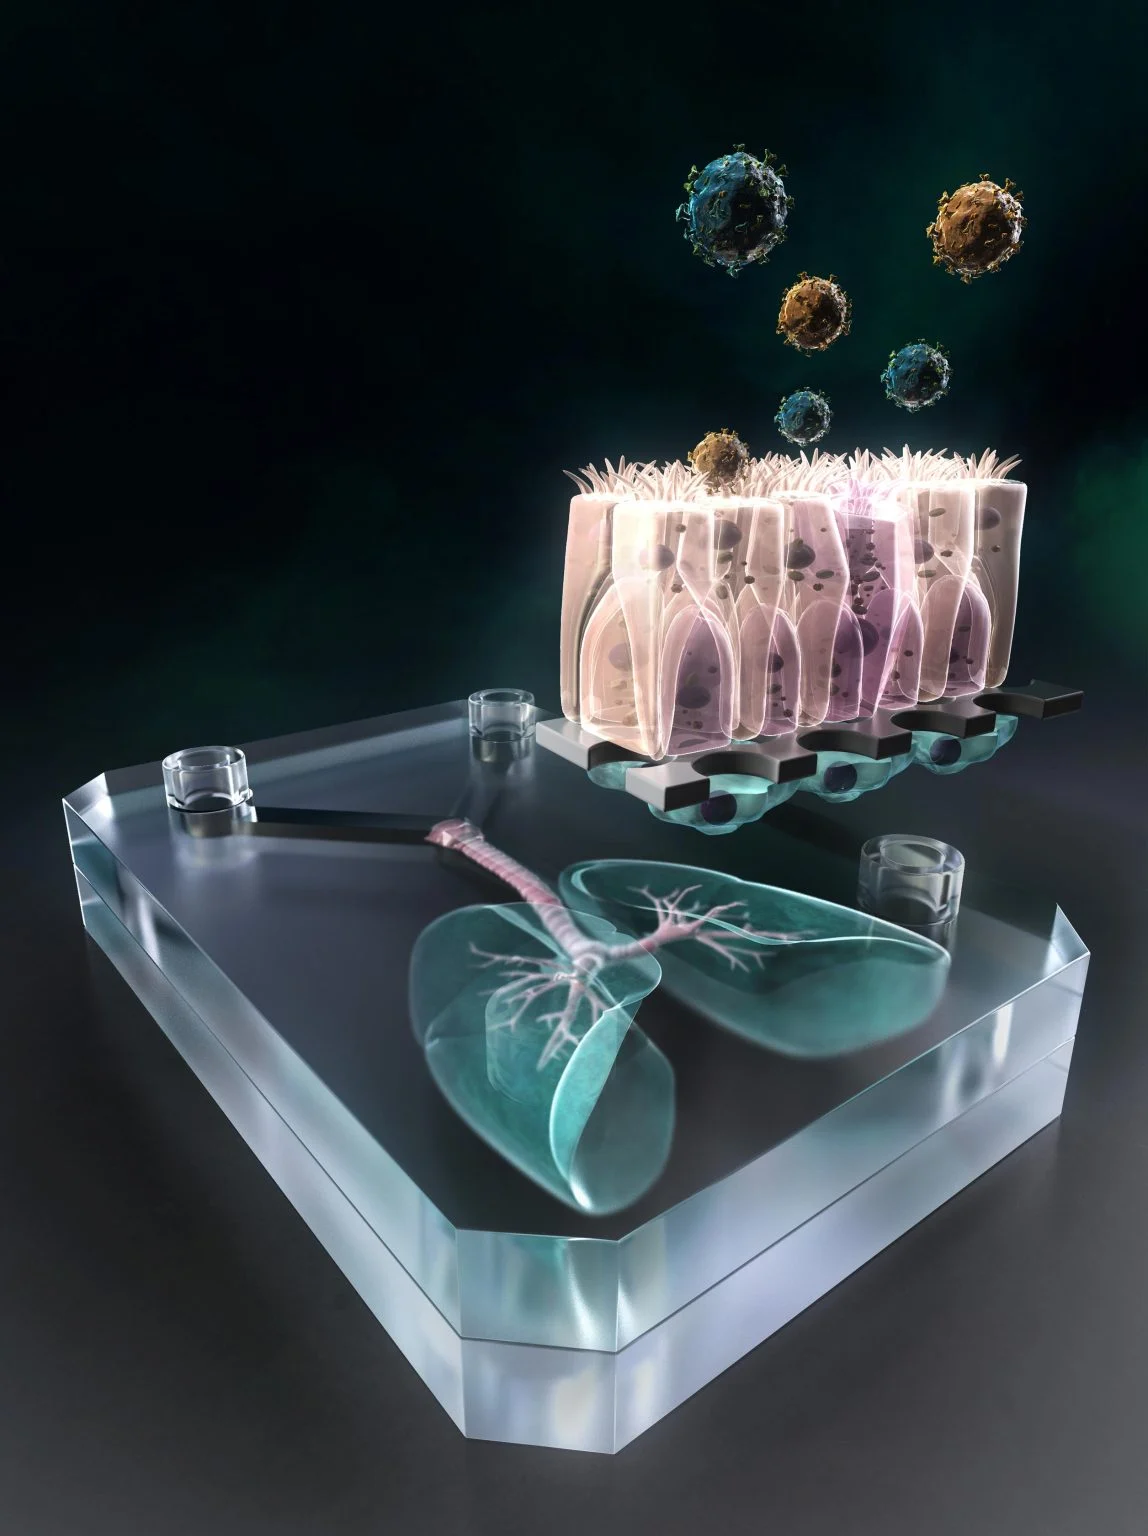

تتجه أنظار الخبراء والسلطات الصحية حول العالم إلى يوم 19 مايو / أيار 2026، باعتباره تاريخاً حاسماً قد يحدد ما إذا كان فيروس «هانتا» الخطير قد بدأ بالفعل في الانتشار خارج نطاق سفينة الرحلات البحرية MV Hondius، التي شهدت تفشياً مقلقاً للعدوى خلال الأسابيع الماضية. فيروس هانتا.. لماذا...